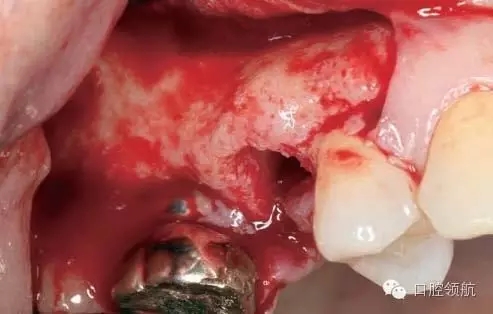

術(shù)前口內(nèi)未見種植體周圍有炎癥等異常表現(xiàn)(圖2),翻開黏骨膜瓣后,10年前手術(shù)入路的痕跡在頰側(cè)骨面已經(jīng)觀察不到了(圖3)。

圖3 黏膜剝離后的口內(nèi)像。10年前手術(shù)入路的痕跡在頰側(cè)骨面已經(jīng)看不到。